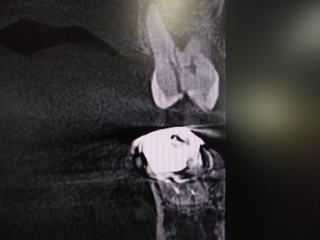

レントゲンでは不明な根尖病巣がCTでははっきり写ります。

同じ患者様です。根管が樋状根になっているのもわかります。